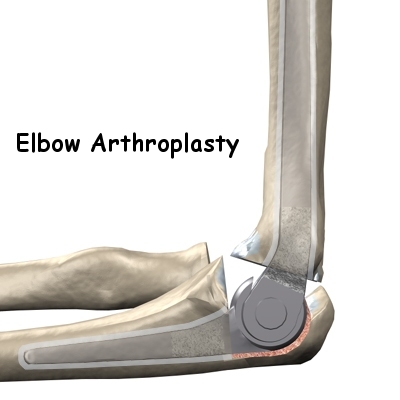

Total Elbow Replacement: Replacing the elbow with an artificial elbow replacement is the "fall-back" operation if treatment of an elbow fracture fails and the elbow is stiff, sore and arthritic. With some very severe elbow fractures one can see "failure" coming right from the beginning. A few surgeons advocate elbow replacement immediately if the elbow is fractured too badly to expect a good outcome with ORIF. If you have pre-existing arthritis of the elbow and a severe injury it may be worth discussing this option with the treating team.

The first line of treatment for elbow arthritis is medication, pain relievers, and NSAIDs. Sometimes an operation to remove spurs and loose bodies is helpful. In progressive cases an elbow replacement is the best solution.